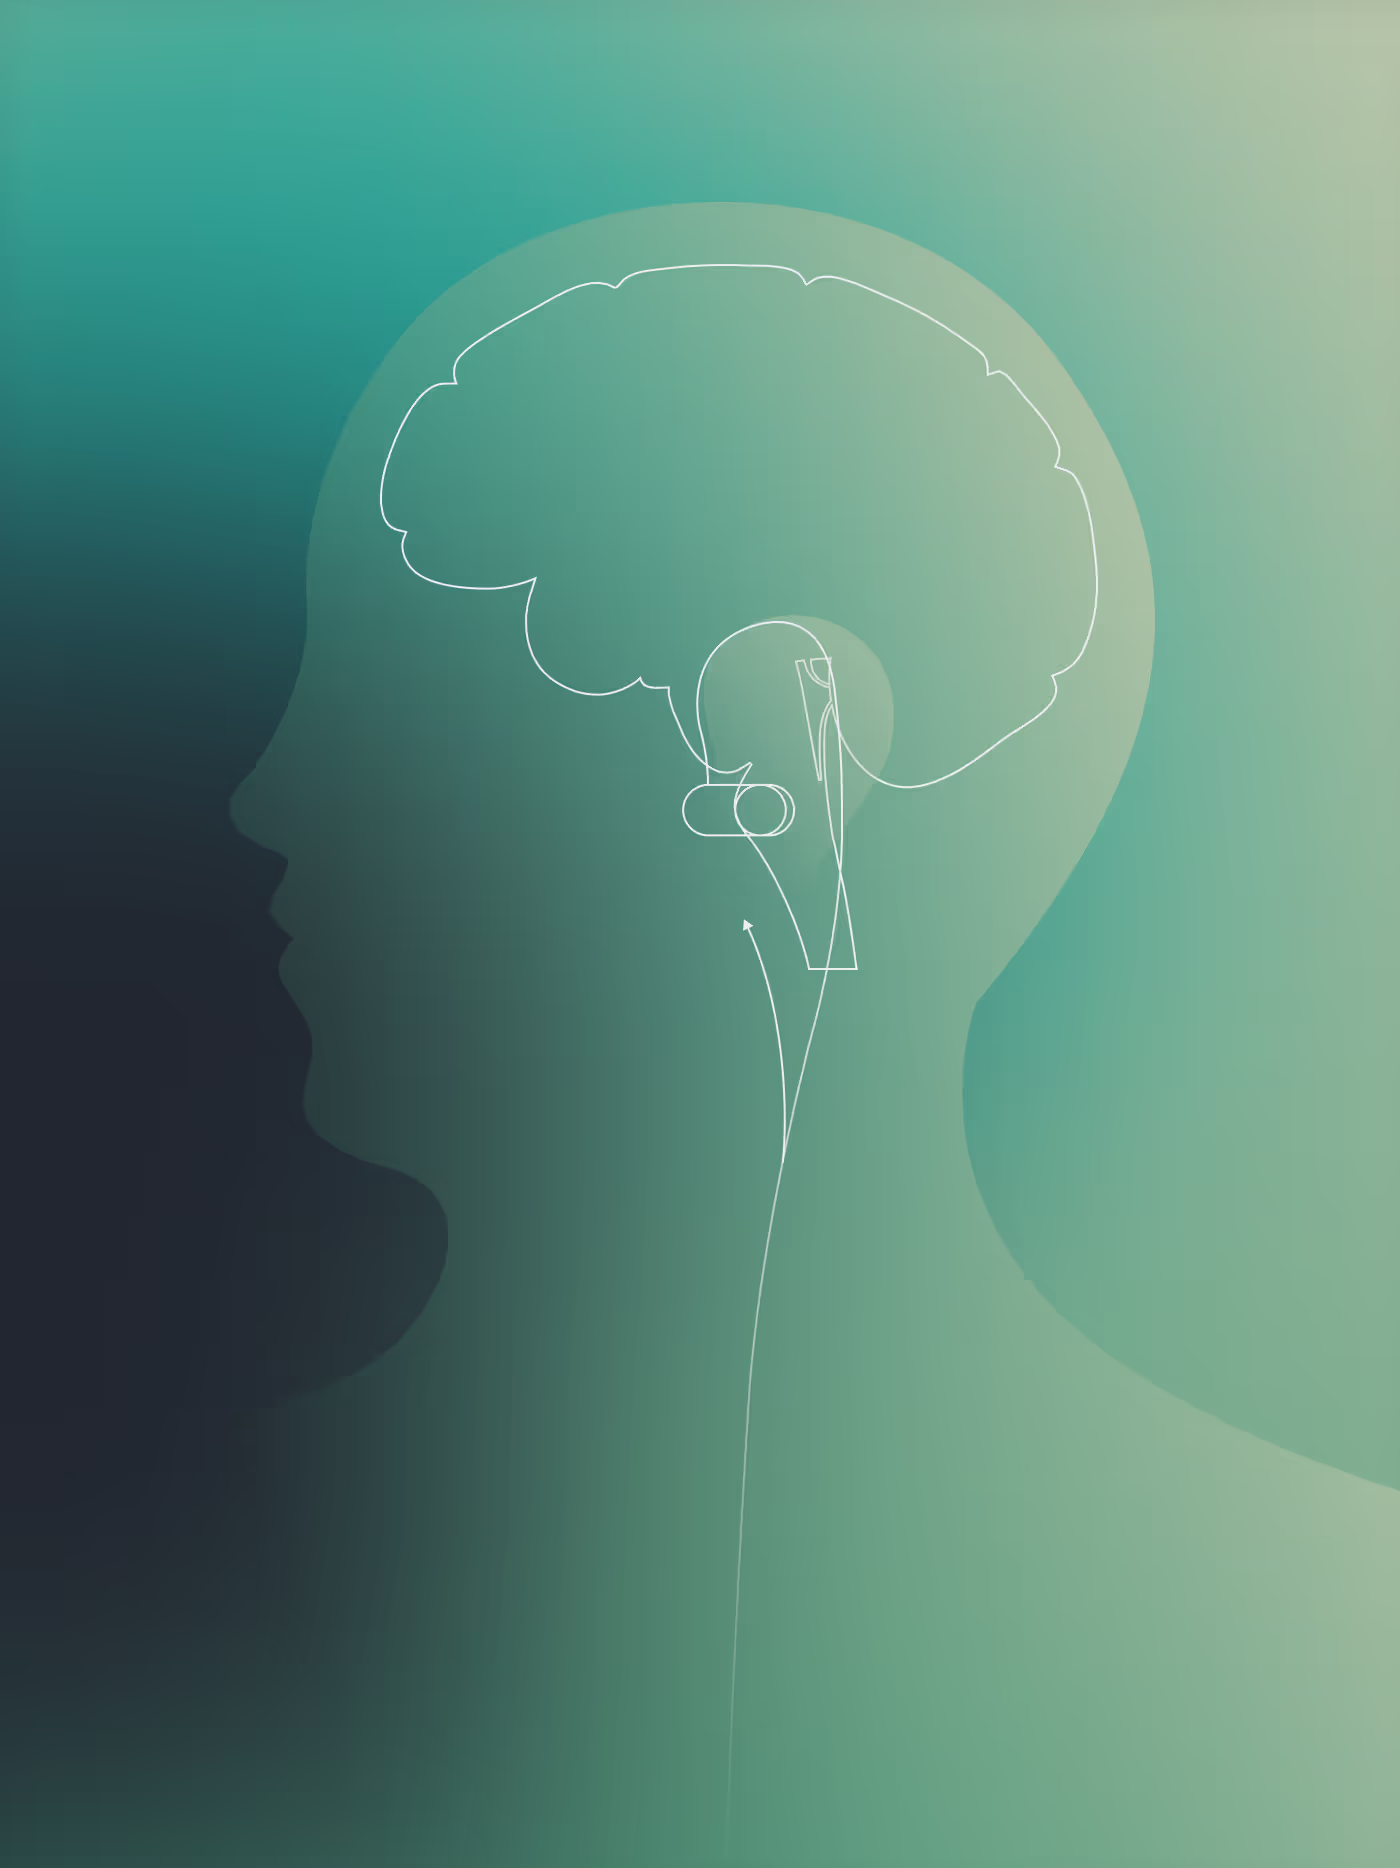

AVNT™, technology to regulate and rewire the stress and inflammatory pathway

Precision Targeting

of the Brainstem

Precise Brainstem Targeting

Afferent signals directly reach the brainstem for optimal impact.

Optimized Signal Delivery

Proprietary gold composite electrodes ensure superior performance.